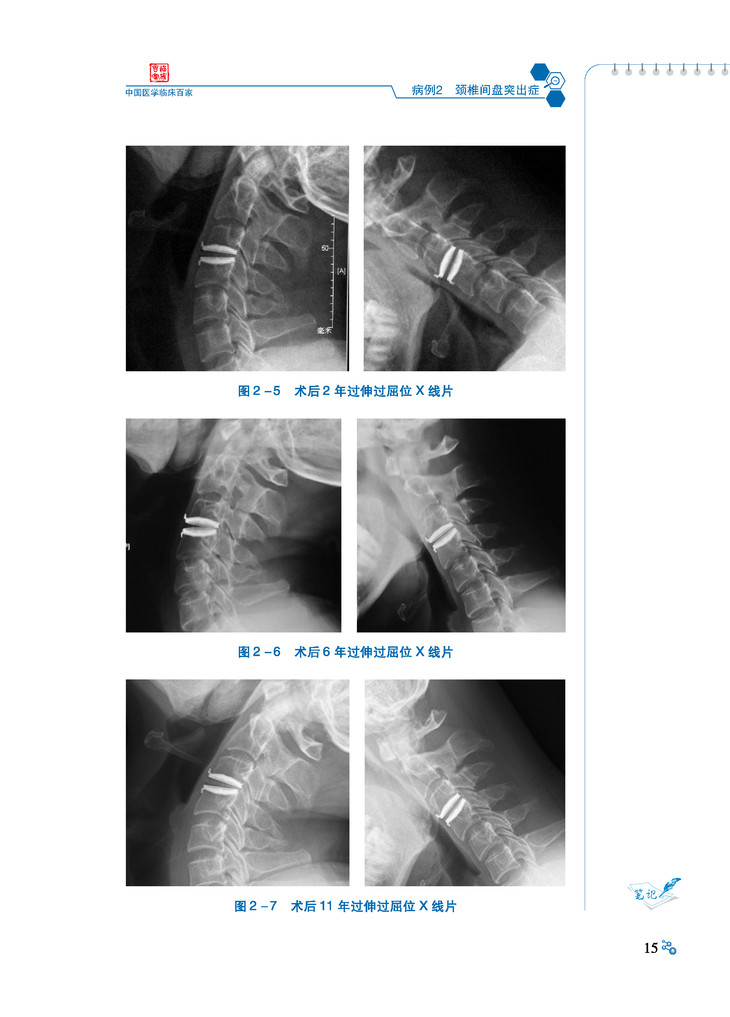

本书汇集了北京大学第三医院骨科近年来收治的典型临床病例,内容涵盖了脊柱外科、创伤外科、关节外科、运动医学外科、骨肿瘤外科、足踝外科、手显外科等亚专科,精选了骨与关节退变性疾病、创伤、肿瘤、感染、畸形等方面的典型病例。这些病例既有常见疾病,也有少见病和疑难病。每个病例均从病例介绍、病例分析、病例点评三个方面着手,旨在通过每一个病例,系统阐述相关知识要点,剖析临床诊疗思路,总结经验教训,值得阅读学习。